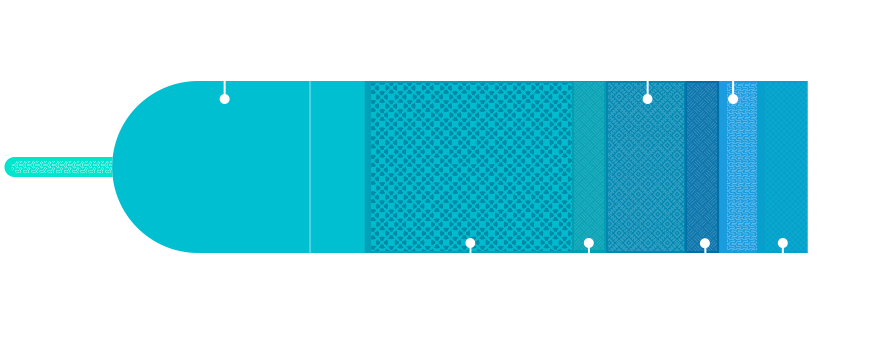

先进探头技术

IBS探头技术

I:Increase Matching Layers,匹配层+,增加匹配层至三层,更好的提升探头的灵敏度和带宽;

B:Bonding Process,邦定加工技术,通过均匀粘接工艺,连接陶瓷和电极的胶层厚度控制在最大1um以内,以改善阵元间的性能一致性;

S:Super Elements,超级阵元,通过超精密加工,一个阵元被分为若干子阵元(最小尺寸为75um)以增加探头的灵敏度和带宽;

以上三种简称IBS探头技术

IBS技术使得探头灵敏度和带宽均提高40%,一致性提升37%,长期稳定性提升42%